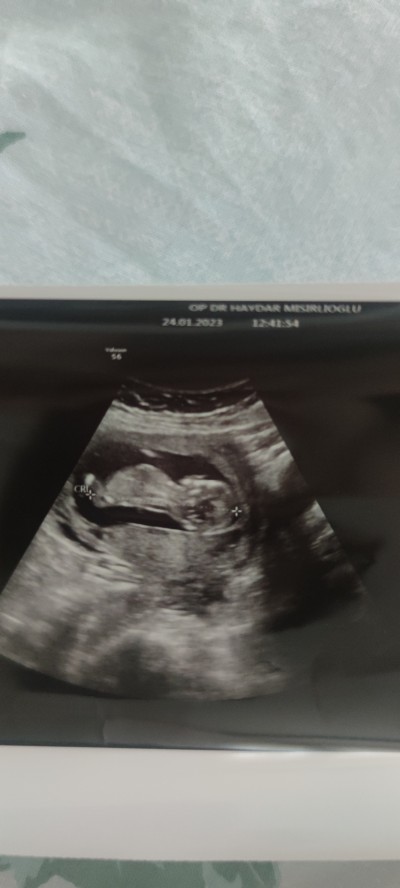

_Kız mı _erkek mi ♥️

12+2 cinsiyet tahmini

Kız geldi içimden Bılmıyorum artıkkk ♥

Bende kiza benzettim